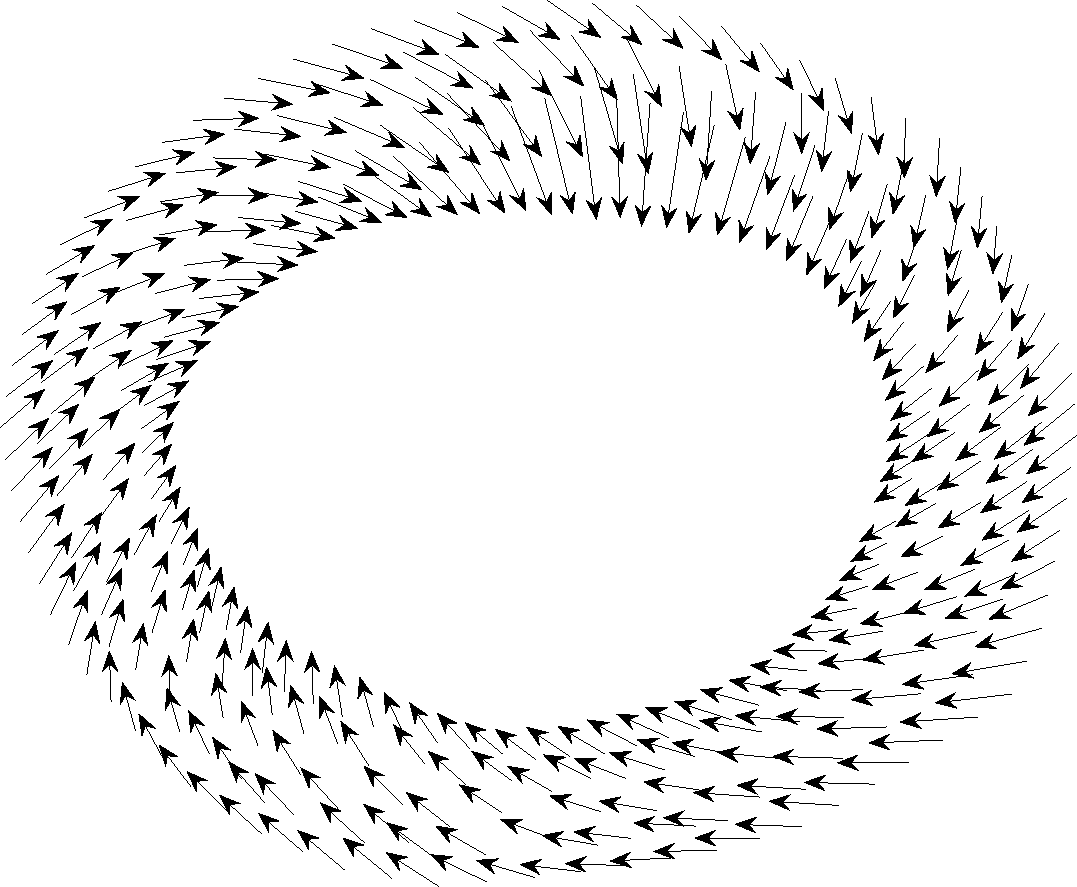

In accordance with the center, contour points can be ordered based on the angle of the crossing line between the point and the center and horizontal axis. Fig. 1 shows the procedure.

Inner and outer contours in MRI images are determined with hand by [23]. Each contour consists of 32 points. The goal here is to find the one-to-one correspondence between contour points between frames. The resolution of the data points is increased by interpolation. Another thing to consider here is that the deformation of heart muscle is not only a concentric radial deformation, but it also contains rotation. On average, during systole, the cardiac muscle has a 7 degree clockwise rotation which needs to be considered in finding one-to-one correspondence and displacement vectors’ computation. The contour points are then down-sampled to reduce the computational complexity. Fig. 8 displays the displacement vectors of one slice of MRI data for subjects 23 (b) and 18 (a) during systole. The existence of MI has a visible effect on the deformation of cardiac muscle.